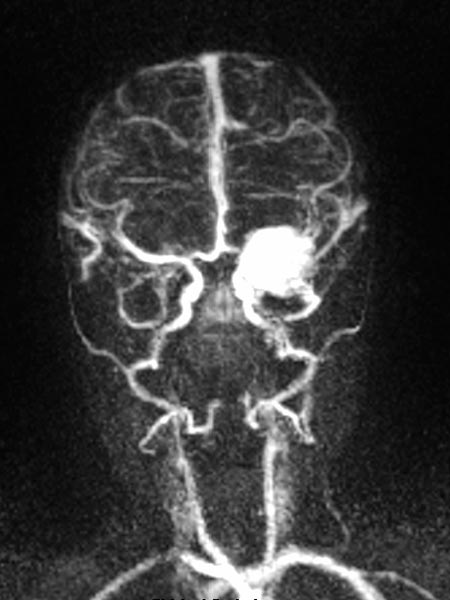

Dynamic contrast-enhanced MR angiography of the skull and cerebral vessels. In the very early arterial phase (A) no yet enhancement of the lesion in the left eye.

Dynamic contrast-enhanced MR-angiography in the arterial phase, 5 seconds later, depicts early and intense enhancement of the tumor in the left eye.

Dynamic, contrast-enhanced MR angiography, early venous phase. The strong enhancement remains, venous drainage via the facial veins and the left-sided external jugular vein.